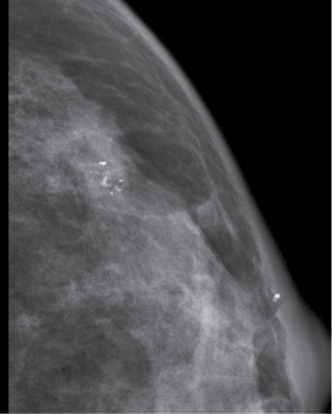

Multivariate analysis showed that calcification with a range > 2 cm (OR: 1.878 95% CI: 1.150–3.067) or calcification with a diameter > 0.5 mm (OR: 2.206 95% CI: 1.235–3.323) were predictive of the HER2 subtype (Figure 2). The model showed good discrimination for prediction of the HER2 subtype (C-index: 0.704). In addition, multivariate analysis showed that calcification morphology (amorphour or coarse heterogenous calcifications OR: 2.847 95% CI: 1.526–5.312; Figure 3) was independently predictive of Luminal A subtype (C-index: 0.74). And we demonstrated that amorphour or coarse heterogenous calcifications were associated with a higher incidence of Luminal A subtype than pleomorphic or fine linear or branching calcifications. We did not detect significant differences in imaged calcification patterns among the breast cancer subtypes (Luminal B vs. other; Basal vs. other). The results of the multivariate logistic regression analysis are shown in Table 3.

Figure 2: Infiltrating ductal carcinoma associated with microcalcification(Feature C:calcifications with > 2 cm in range and Feature D:calcifications with > 0.5 mm in diameter).